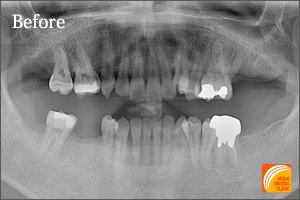

症例3

Before

期間 :3カ月

回数 :4回

費用 :410,400円

内容 :インプラント1本、GBR、セラミック冠1本分含む

After

右下奥歯に1本のインプラントを埋入した患者さんです。前後の歯の状態が良くないため普通のブリッジは適応不可でしたが、1本のインプラントを埋入することにより前後の歯の寿命を伸ばすことが可能になります。